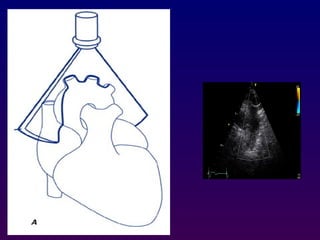

Parasternal long axis

With the transducer in the 3rd or 4th right intercostal

space immediately adjacent to the sternum and

patient in left lateral decubitus a long-axis view of

the heart is obtained which bisects the aortic and

mitral valve, Proper positioning of the probe results

in the ascending aorta being relatively horizontal in

orientation.